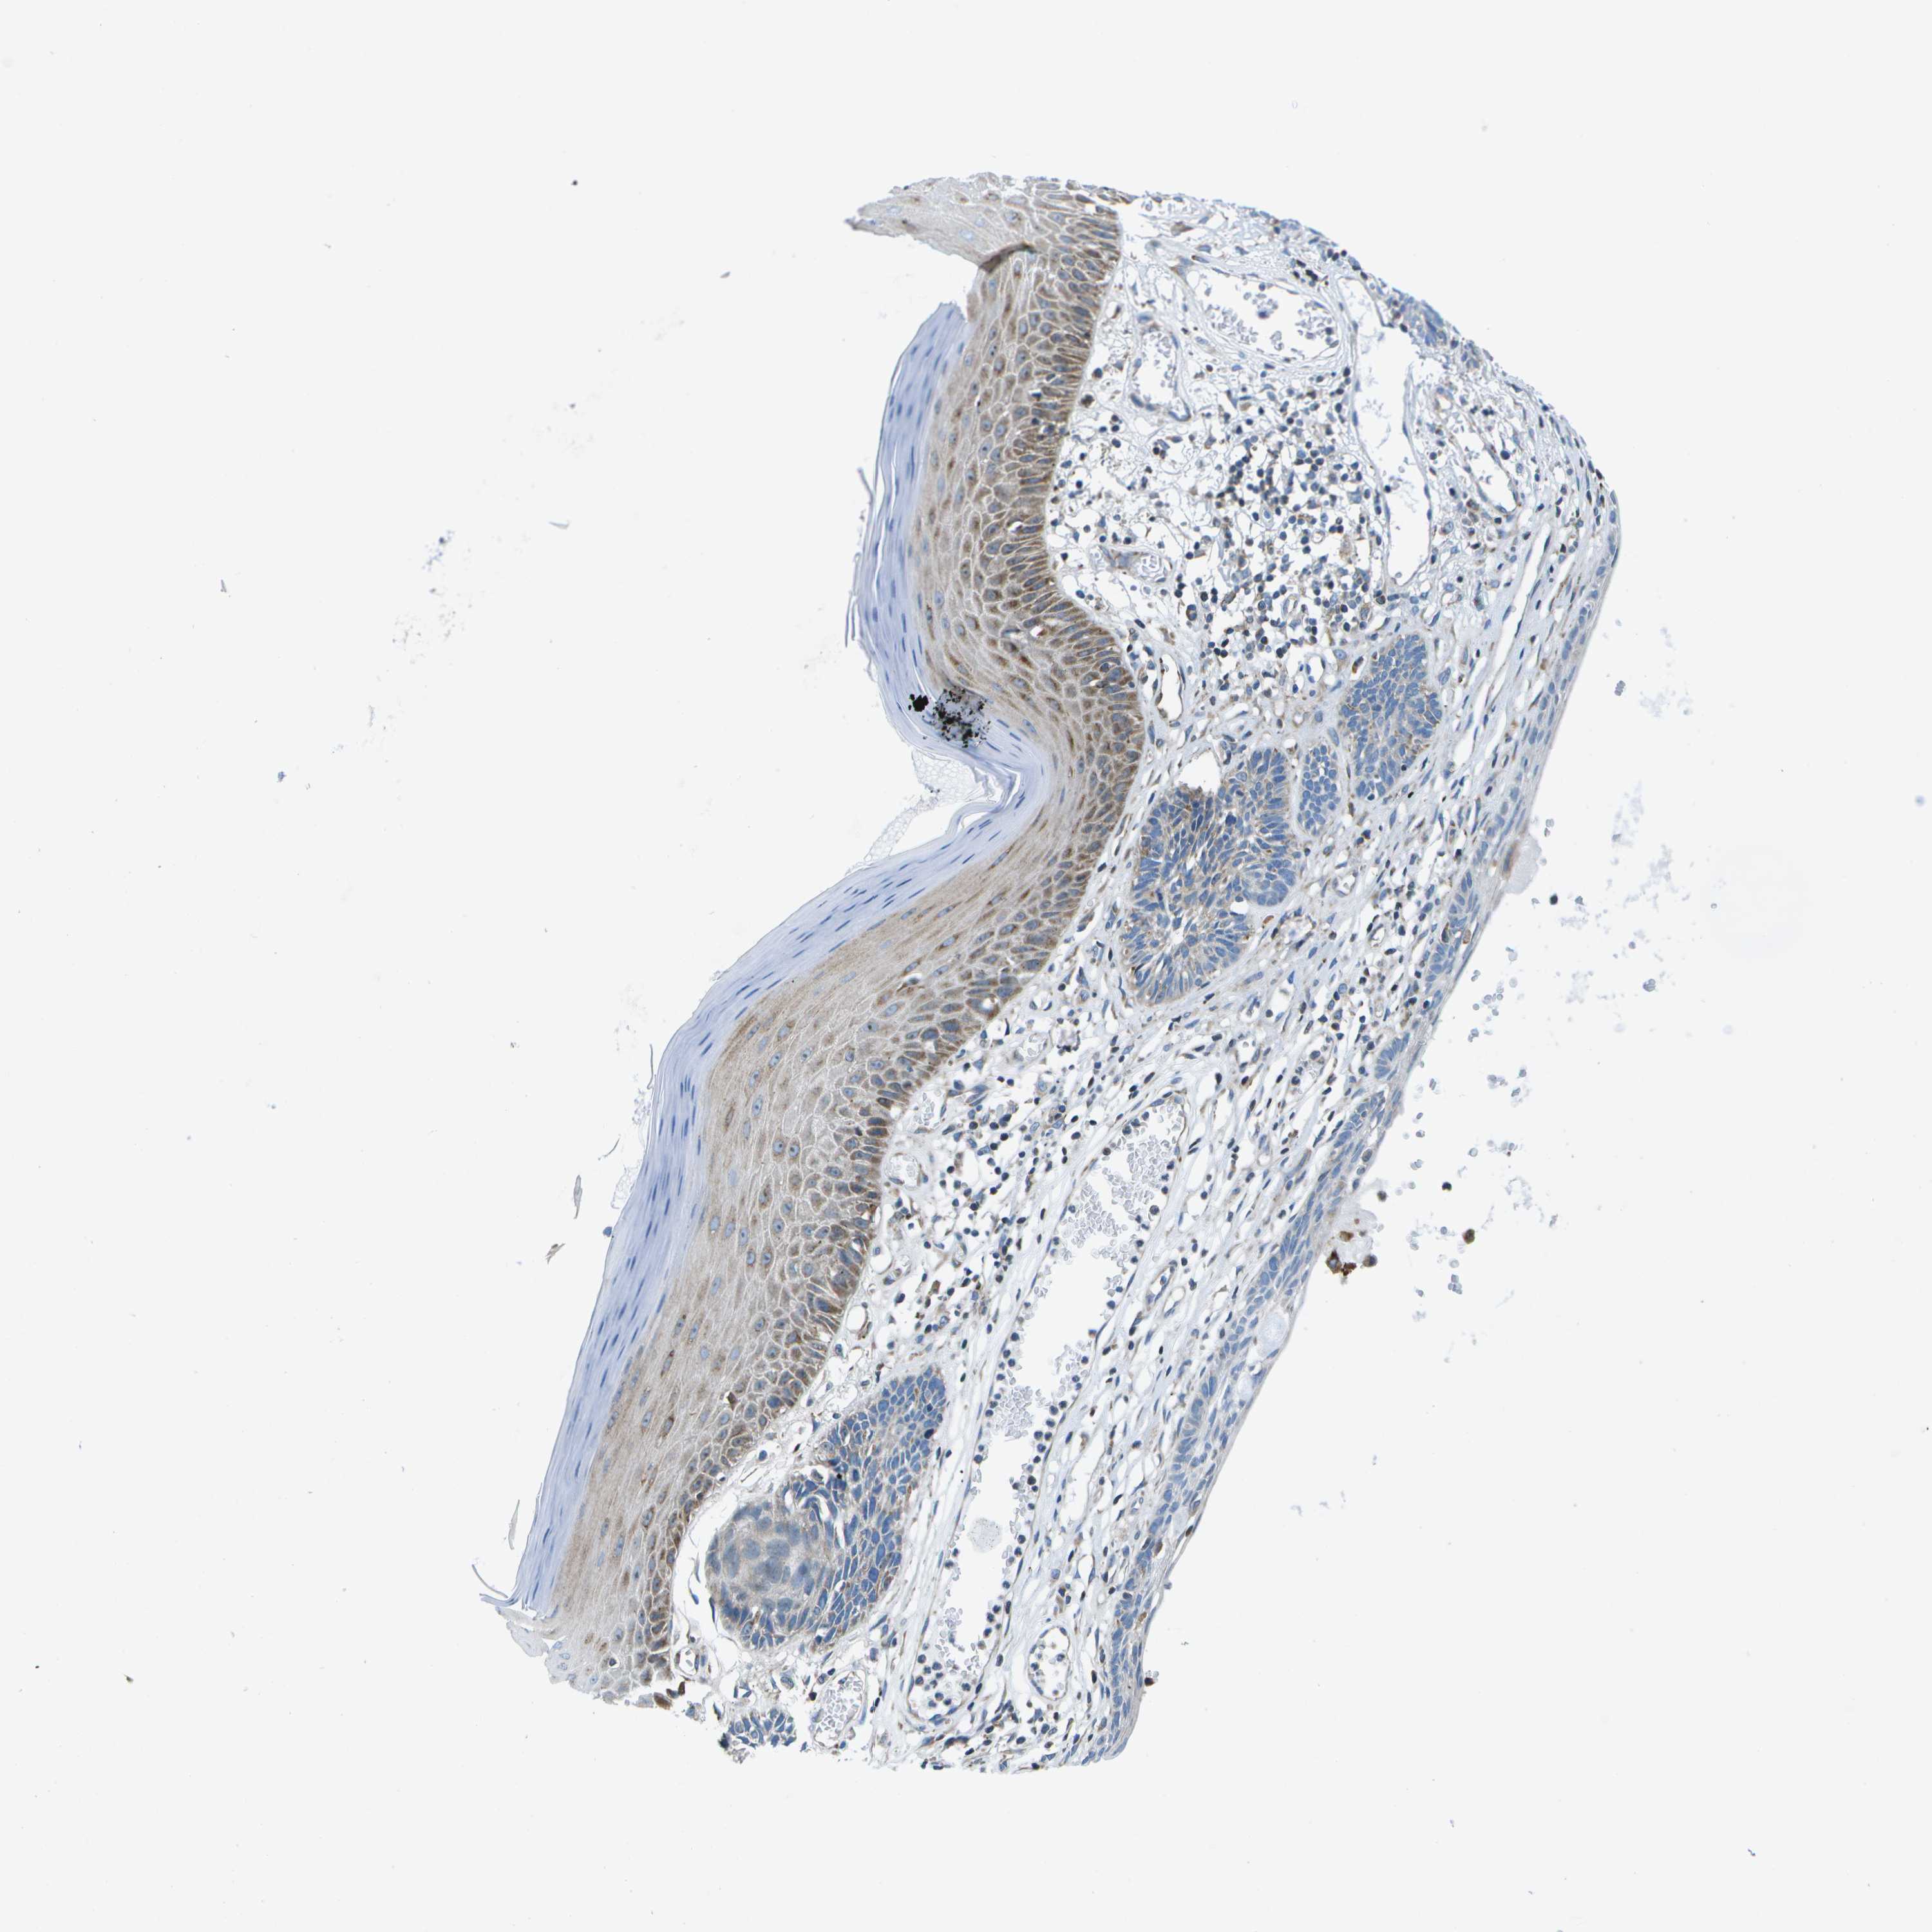

SKIN CANCER - Protein expressioni

A mouse-over function shows sample information and annotation data. Click on an image to view it in a full screen mode. Samples can be filtered based on level of antibody staining by selecting one or several of the following categories: high, medium, low and not detected. The assay and annotation is described here.

Antibody stainingi

Antibody staining in the annotated cell types in the current human tissue is reported as not detected, low, medium, or high, based on conventional immunohistochemistry profiling in selected tissues. This score is based on the combination of the staining intensity and fraction of stained cells.

Each image is clickable and will lead to virtual microscopy that enables deeper exploration of all samples and also displays staining intensity scores, fraction scores and subcellular localization as well as patient and tissue information for each sample.

Antibody HPA015648

Staining

High

Medium

Low

Not detected

Intensity

Strong

Moderate

Weak

Negative

Quantity

>75%

75%-25%

<25%

None

Location

Nuclear

Cytoplasmic/membranous

Cytoplasmic/membranous,nuclear

Squamous cell carcinoma in situ, NOS

Squamous cell carcinoma, NOS

Squamous cell carcinoma, metastatic, NOS

Basal cell carcinoma

Adnexal tumor, benign